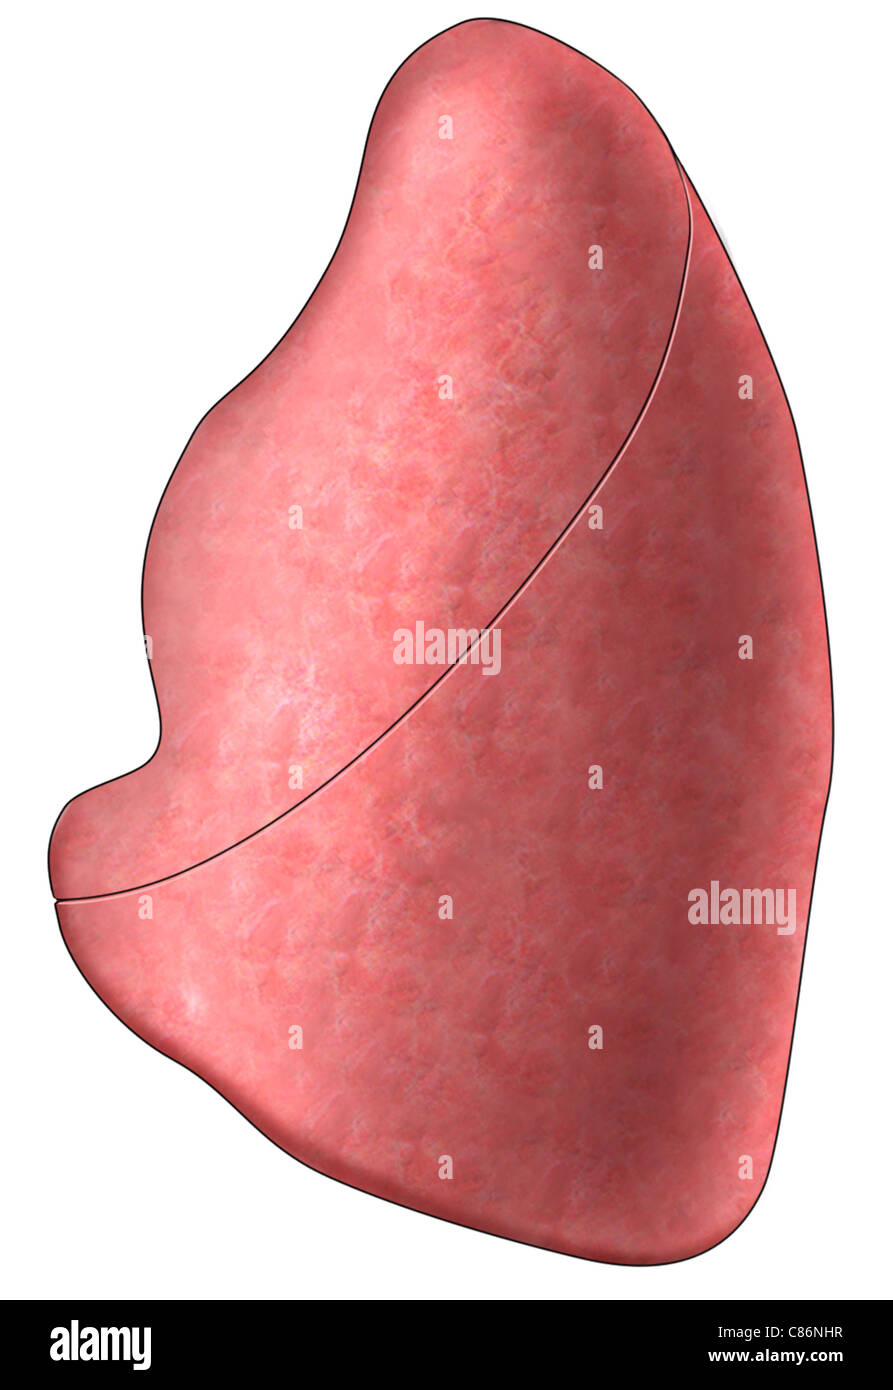

Left Lung - Side View Stock Photo - Alamy

lung left side alamy stock